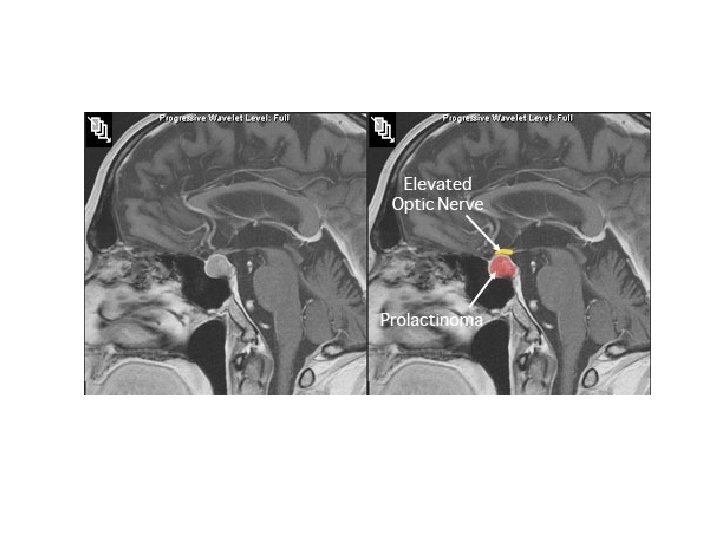

A 35 year-old-female presents to her gynecologist after missing her period for the past 3 months. She is sexually active and uses condoms for contraception but has not had a sexual partner in the last year. She also reports that her breasts have been leaking milk for some time. Physical examination is normal. A head MRI is shown. Which of the following structures would most likely be jeopardized if the tumor continues to increase in size? a. Optic chiasm b. Fourth ventricle c. Cerebral aqueduct d. Thalamus e. Caudate nucleus

correct answer: A Prolactinomas are prolactin-secreting tumors of the anterior pituitary, classically presenting with galactorrhea and amenorrhea or infertility in pre-menopausal women. Amenorrhea occurs due to prolactin’s inhibition of LH, as well as Gn. RH pulses. Downregulation of Gn. RH leads to a decrease in FSH, and subsequently, estrogen levels leading to anovulation. Fortunately, these effects lead to their early detection in premenopausal women compared to their male and post-menopausal counterparts. In the latter populations these tumors tend to be of greater size and do not come into clinical attention until they are large enough to affect adjacent structures. The optic chiasm (Option A) is located directly above the pituitary gland can be compressed leading to blindness. None of the remaining options are near the pituitary gland therefore are less likely to be affected by these tumors.